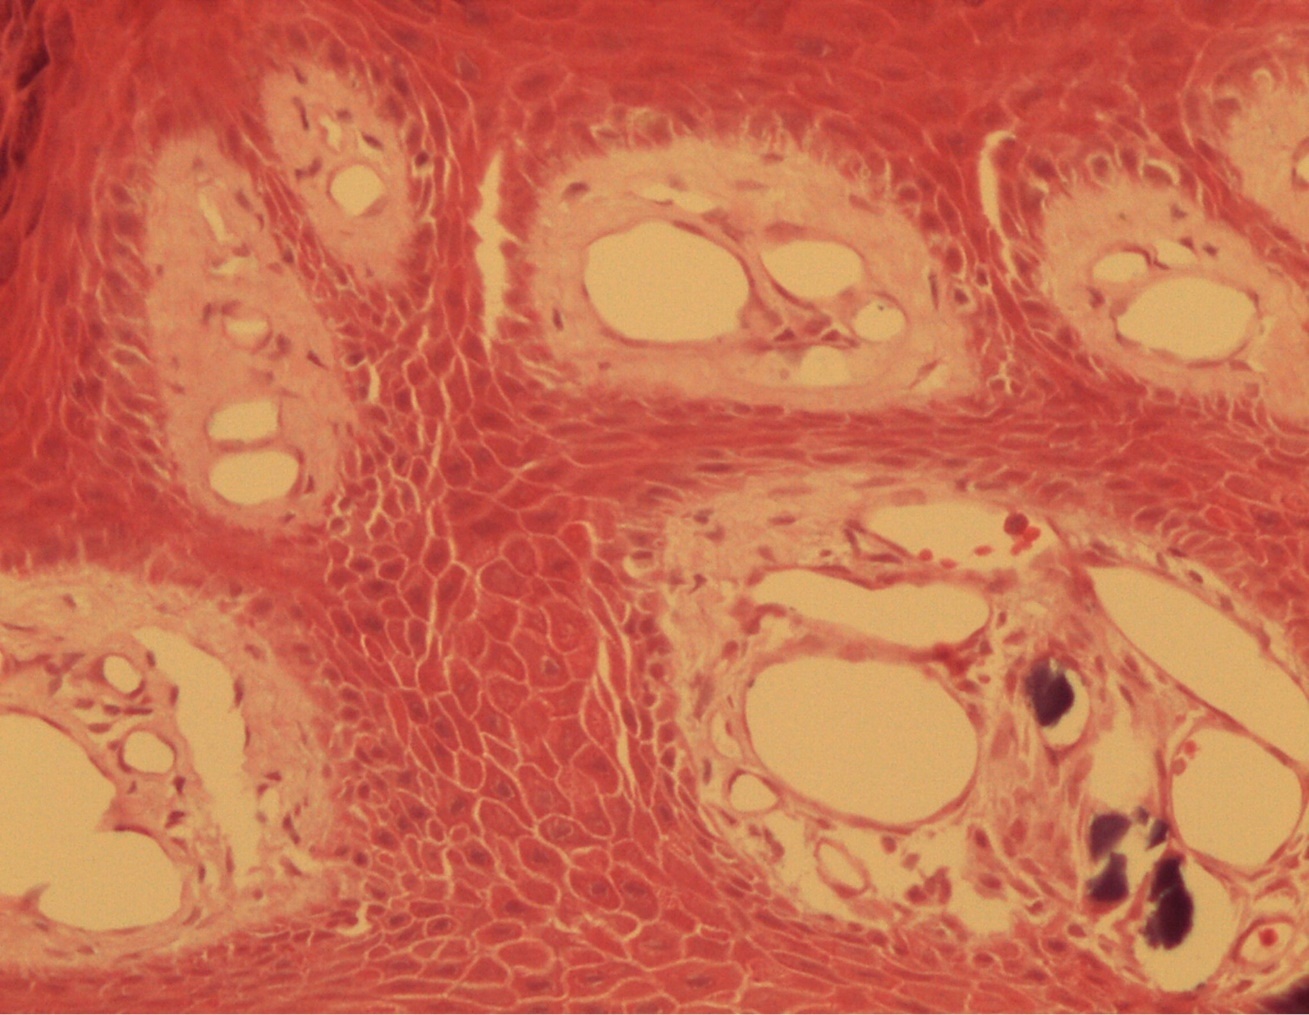

A 9-year-old male patient who was treated in the dermatology service for a progressively growing keratotic nummular dermal lesion on the right knee. With the clinical judgment of viral wart, the lesion was removed. In the Pathology Service, a nummular keratotic lesion of 0.5 cm in maximum dimensions was received, which crackled when cut. Figure 1, Figure 2, Figure 3, Figure 4, Figure 5

Figure 2.Common wart with calcium foci at the level of the dermal vessels grouped in lobules. HE. 200x.

Figure 3.Relationship of calcium foci in the papillary dermis with the overlying epidermal hyperplasia. HE. 200x.

Figure 4.Presence of calcium deposits in the dermal vessels. Detail. HE 400x.